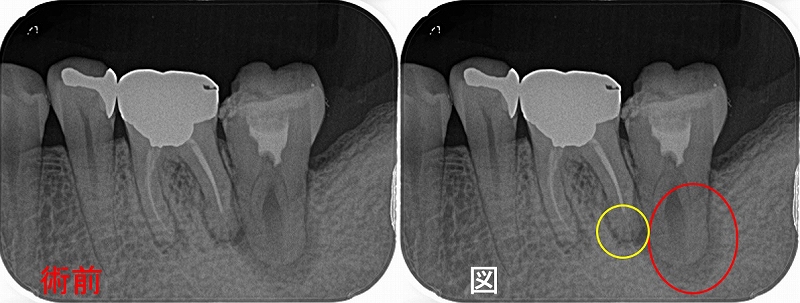

今週1年予後で来院しててもらいました。

レントゲン

2025 EEdental KOE (3).jpg

綺麗に骨が出来上がってくれています!

また1本前の根尖病変に見えた歯の所見も落ち着いているように見えます。